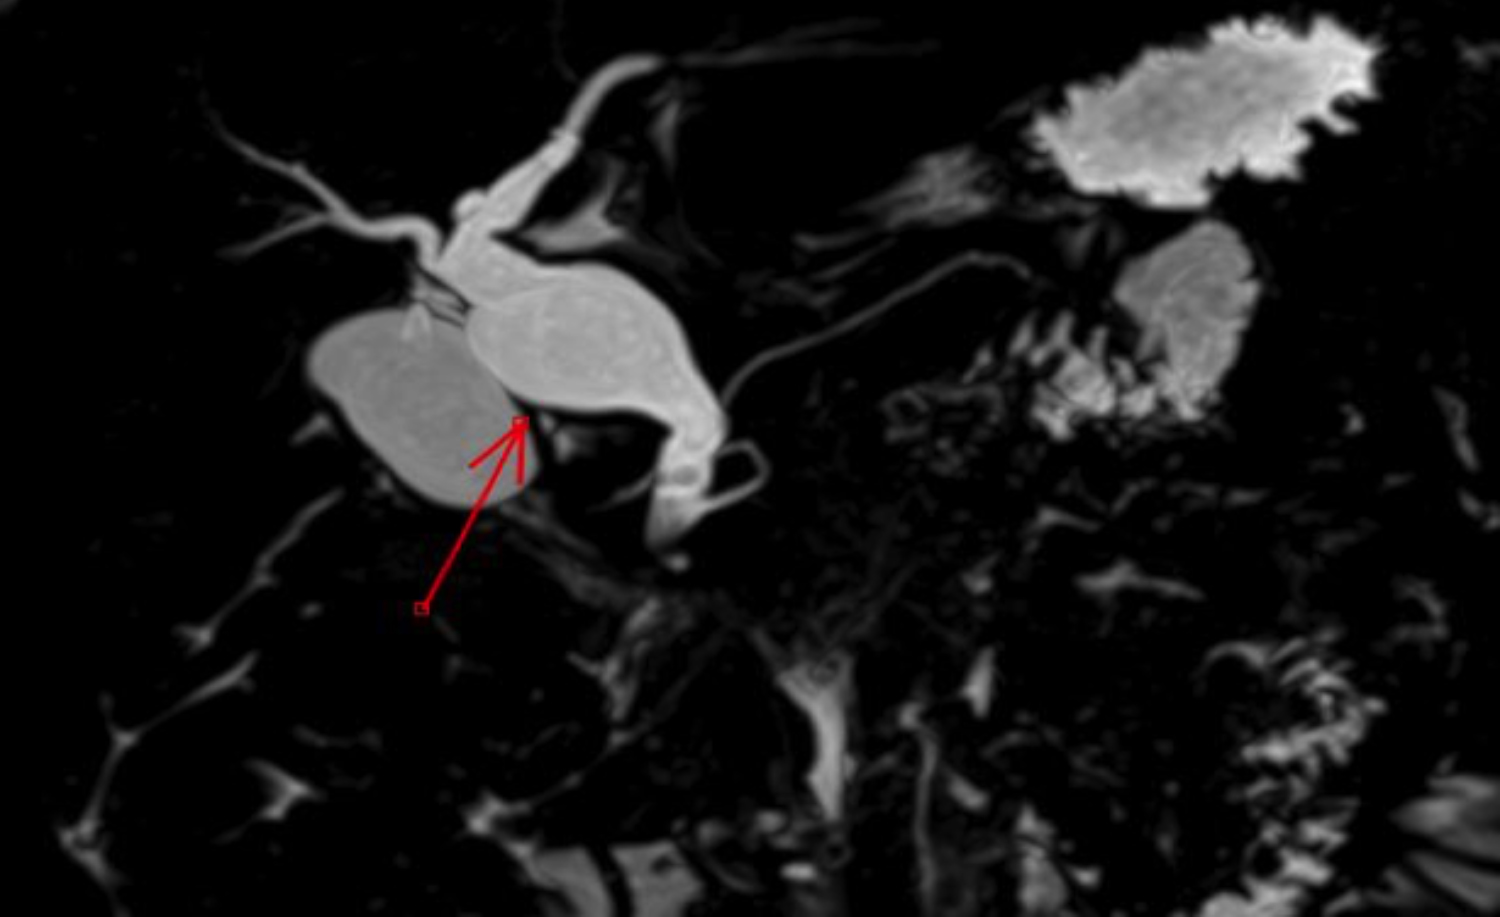

The patient was shifted to the floor, and MRCP was planned. The MRCP showed a dilated, ballooned-out proximal CBD with a calibre reaching up to 15 mm, along with multiple variable-sized internal filling defects likely representing type I choledochal cysts with choledocholithiasis (Figure 1, 2). Mild intra- and extrahepatic biliary dilatation was noted. The pancreatic duct exhibited variant anatomy, with the main pancreatic duct draining via the minor papilla and a small ventral duct draining into the CBD via the minor papilla. There was a rudimentary communication between the dorsal and ventral pancreatic ducts, suggesting pancreatic divisum (incomplete / type III, Figure 3).

Figure 2: 3D reconstructed image of MRCP showing dilatation and ballooning of proximal CBD suggesting choledochal cyst represented by the red arrow. Few filling defects in distal CBD suggest choledocholi- thiasis.

Choledochal cysts with pancreatic divisum are a rare condition. In our patient, the choledochal cyst was categorised as type I according to the Todani classification. MRCP showed a ballooned-out CBD with multiple internal calculi. Pancreatic divisum in this patient was incomplete (Type III), with a small rudimentary communication between the dorsal and ventral pancreatic ducts.